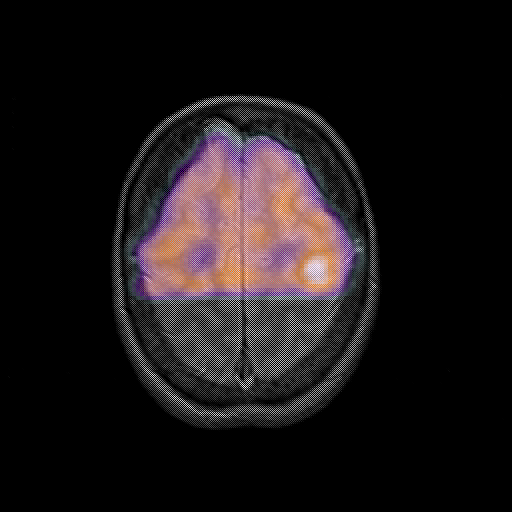

overlay : Slice 43

Slice 43

MRCBFCBF with

T1PDT2T1PDT2